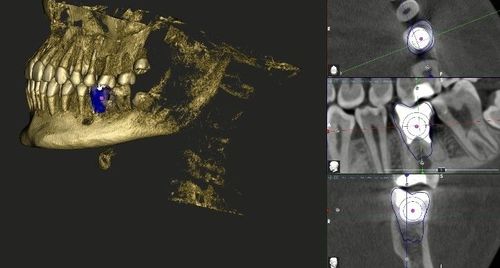

Зуб 3.6 - коронка значительно разрушена, на КЛКТ видим, что каналы зуба раньше лечили, но все равно результат неудовлетворительный: имеется патологическая резорбция дистального корня и очаг инфекции вокруг корней.

Мы провели цифровое планирование: виртуально вырезали зуб 2.8 (верхний ретенированный зуб мудрости) и в специальной программе переместили его на место 3.6.

Затем мы напечатали на 3Д принтере шаблон зуба 2.8 для использования его во время операции для подготовки лунки 3.6.